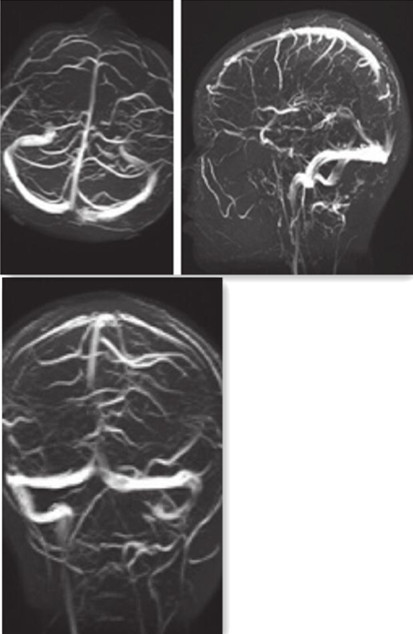

图4 MRV提示上矢状窦近窦汇上方显示不连续,提示受压改变